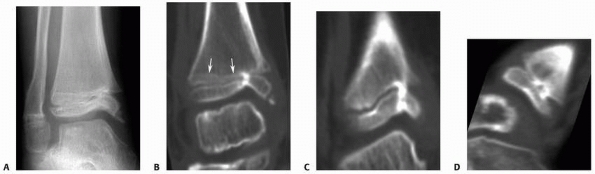

the assessment and treatment of most physeal injuries, occasionally

greater anatomic detail is necessary. CT scans provide excellent

definition of bony anatomy, particularly using reconstructed images.

They may be helpful in assessing complex or highly comminuted

fractures, as well as the articular congruency of minimally displaced

fractures (Fig. 5-29). MRI scans are excellent

| Figure 5-29 CT scans with or without reconstructed images can be helpful in the assessment of physeal fractures. Coronal (A) and sagittal (B) plane reconstructions of a triplane fracture of the distal tibia. |